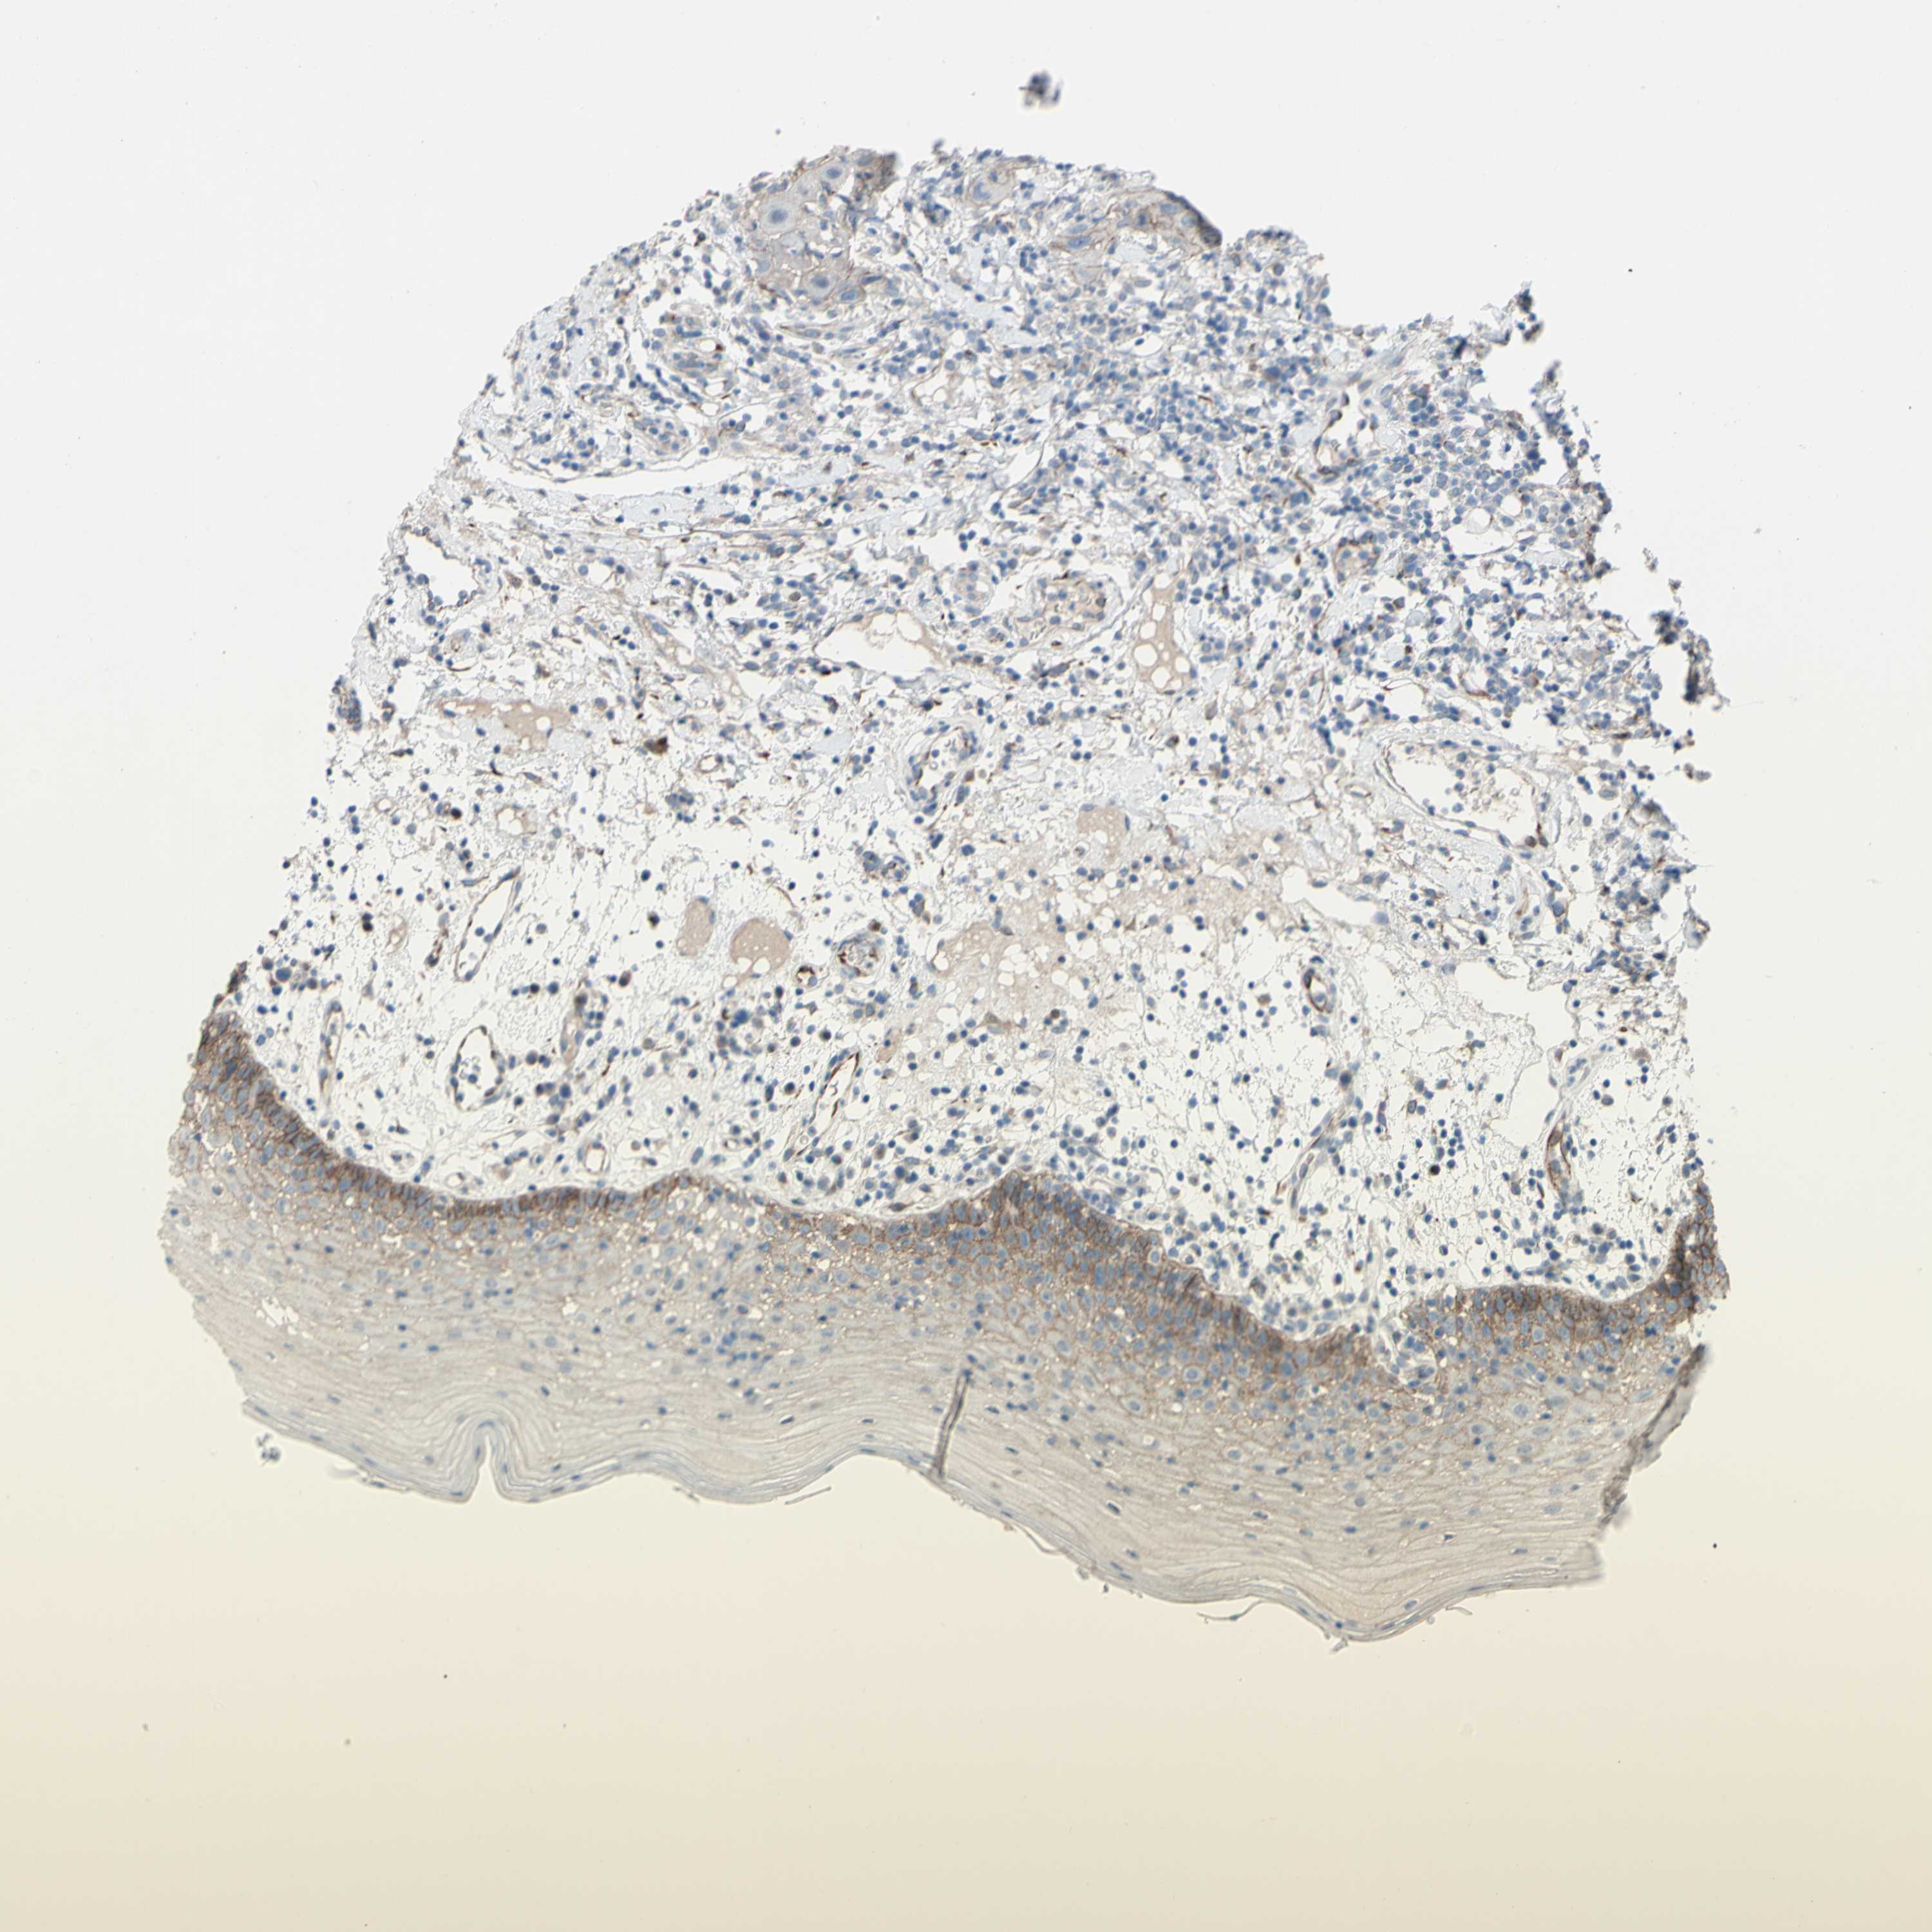

CDCP1